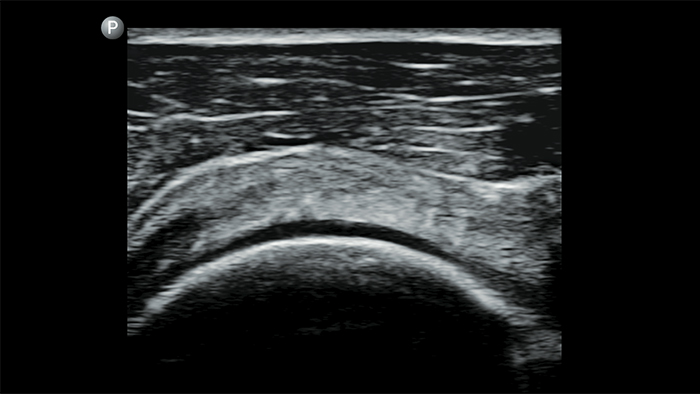

Esté atento a la neumonía por COVID

Lumify puede ayudar a obtener resultados similares a los de una tomografía computarizada de tórax al evaluar la neumonía y el síndrome de dificultad respiratoria en adultos.

Ultrasonido renal focalizado